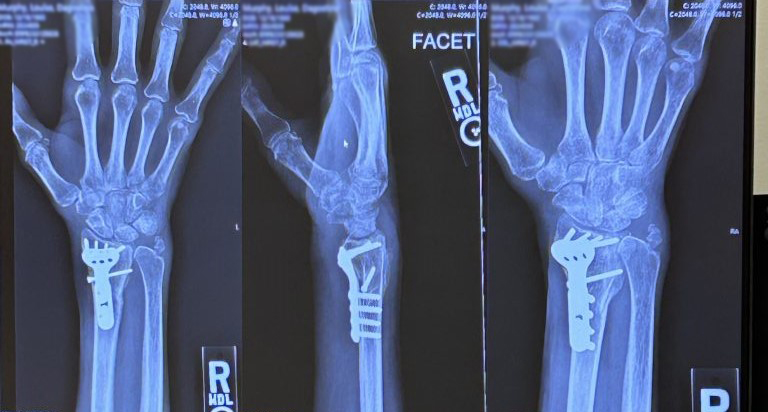

My wrist was deformed. My hand was over there and the rest of my arm was over here, like the letter S (see image). It was like something out of a horror movie - but it was attached to me! The local ER drugged me then moved my hand back into place and told me to see a wrist surgeon in case I needed surgery. I visited two local surgeons in Bucks County, PA, and then went down to a facility in Philadelphia for a third opinion. The first doctor wanted to put me under general anesthesia, which I didn't want. The other two said they would do a local block with twilight anesthesia, which was fine; however, they all told me I needed metal hardware with multiple screws, and that scared the living daylights out of me. I had never had surgery before and, especially, not had any metal implants.

I cannot say enough about Dr. Wolfe. Plenty of doctors are smart and competent, but Dr. Wolfe is a cut above. He has a wonderful, caring disposition, and sat there patiently listening as I cried and said I didn't want surgery. He said he could go the non-surgical route but showed on an x-ray all of the fractures in my wrist, methodically explaining that without surgery, my wrist could collapse later on and wouldn't be stable. He also assured me that the hardware could be removed once the bones were totally healed and he felt it was not a risk removing them.

I was in good hands - literally. Dr. Wolfe has so many impressive credentials; I knew that this was the best doctor I could see for my wrist fracture. The surgery happened a few days later, and everything went smoothly. I returned for the scheduled follow-ups, and at one point, Dr. Wolfe discussed the option of removing the hardware, to which I happily agreed.